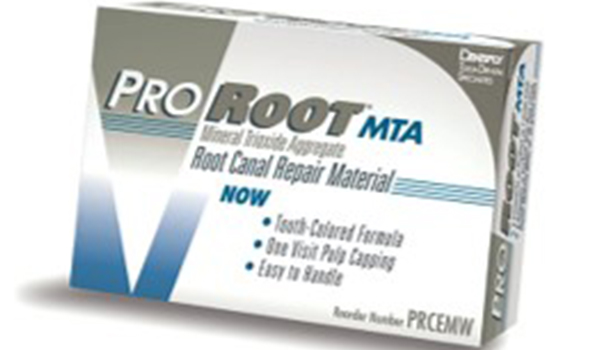

06

MTAセメント

の使用

MTAセメントとは、治療用の材料の1つで、歯の神経を残す治療に有効です。

根管治療は歯の神経を取る治療のため、栄養が届かなくなることで歯が脆くなり、結果的に歯の寿命が短くなる可能性が高くなります。

しかし、穴やヒビを塞ぐMTAセメントは、封鎖性が高く、殺菌作用があります。また生体親和性に優れているため、周囲の細胞を再活性させることが可能です。それらによって、むし歯が進行したところまでの組織を取り除き、MTAセメントで塞ぐことで、神経の生活反応を残したまま保存することが可能です。

MTAって何ですか?

根管治療で歯を残す可能性を高める、特別なセメントです。

MTA(Mineral Trioxide Aggregate)は、根管治療の分野で大きな進歩をもたらした材料です。

従来のセメントに比べて封鎖性が高く、細菌の再感染を防ぐ力が強いことに加え、歯や骨の再生を助ける作用もあります。

最初に登場したMTAは操作が非常に難しいものでしたが、その後さまざまな改良型製品が開発されてきました。

当院では、症例ごとに複数のMTAを使い分け、最も治癒に導ける方法を選択しています。

ただし、MTAは非常に高価で保険では使用できない場合が多いため、精密な自費治療において積極的に導入しています。